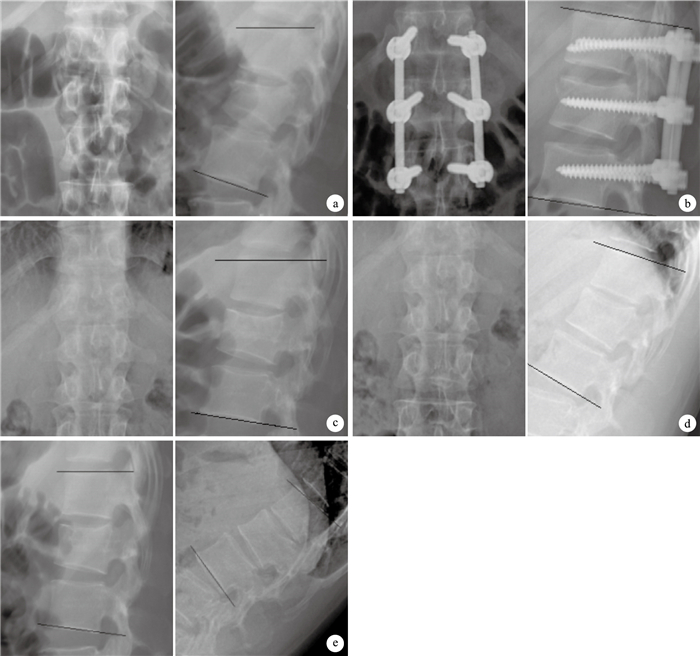

兩組手術均由同一組醫師完成。氣管插管全麻后,患者取俯臥位。作后正中切口,長約7 cm;無神經損傷體征者采取肌間隙入路;有神經損傷體征者,非減壓側采取肌間隙入路、減壓側采取正中入路。固定傷椎和上、下相鄰椎體,通過螺釘和撐開連接棒恢復椎體高度、糾正后凸畸形。融合組將傷椎雙側椎板去皮質,破壞雙側關節突關節,橫突去皮質,取自體髂后上嵴松質骨,將雙側橫突及關節突、椎板融合(圖 1)。非融合組不作其他處理。術畢逐層縫合,關閉切口。